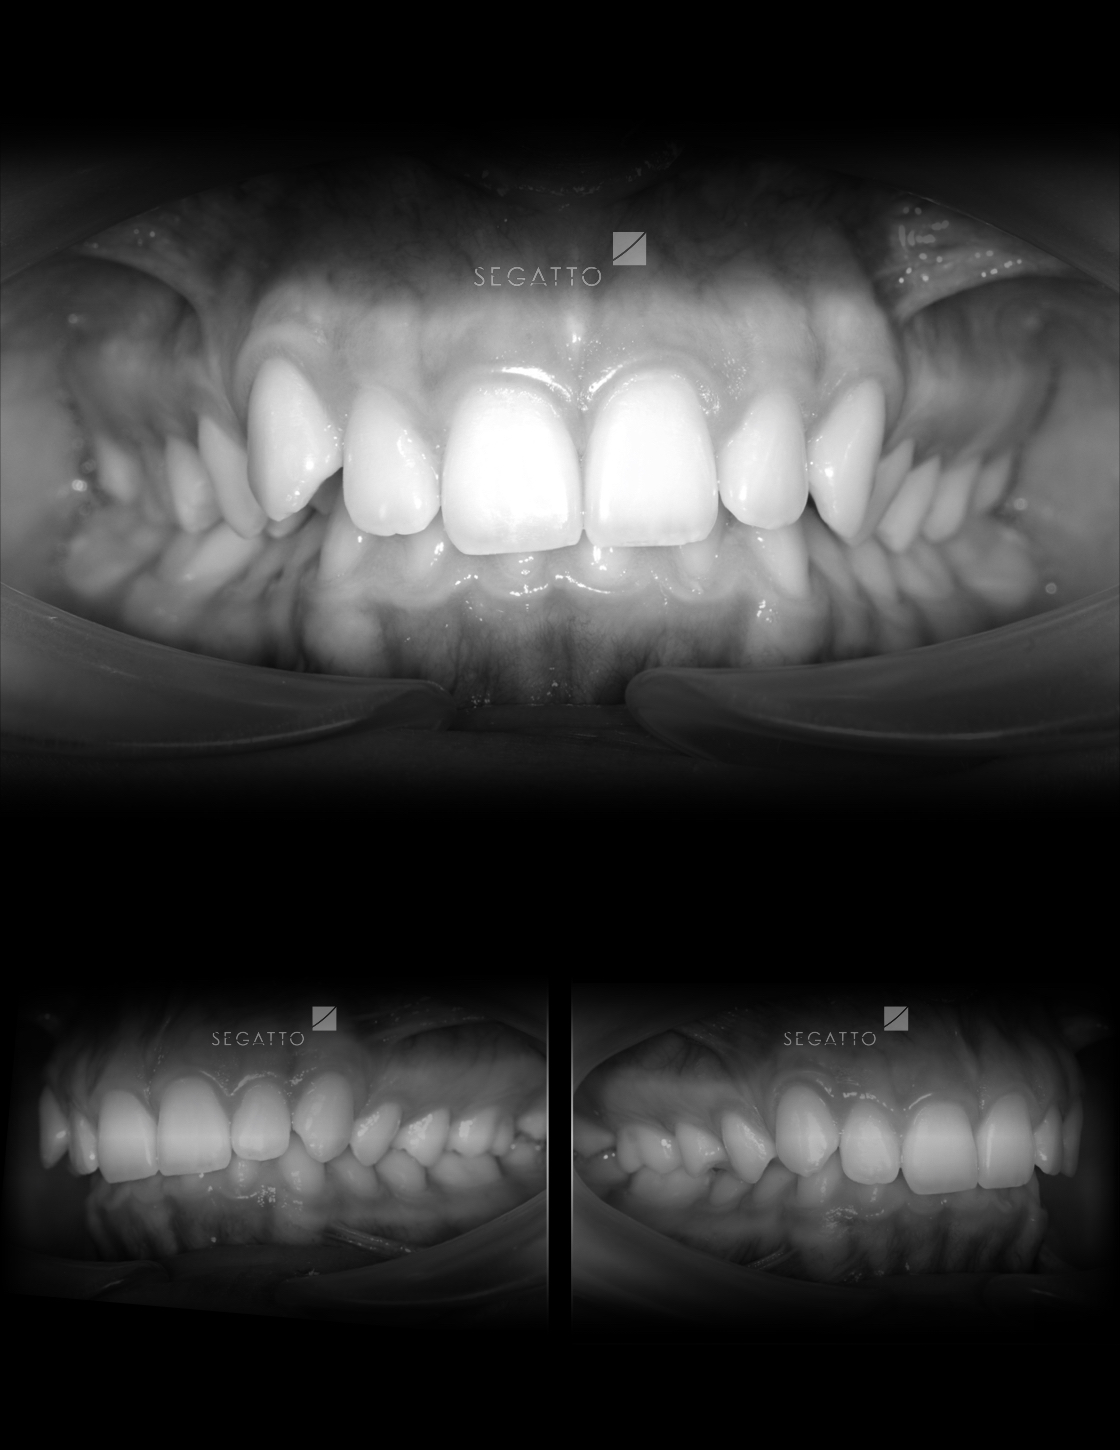

Orthodontics

Cases